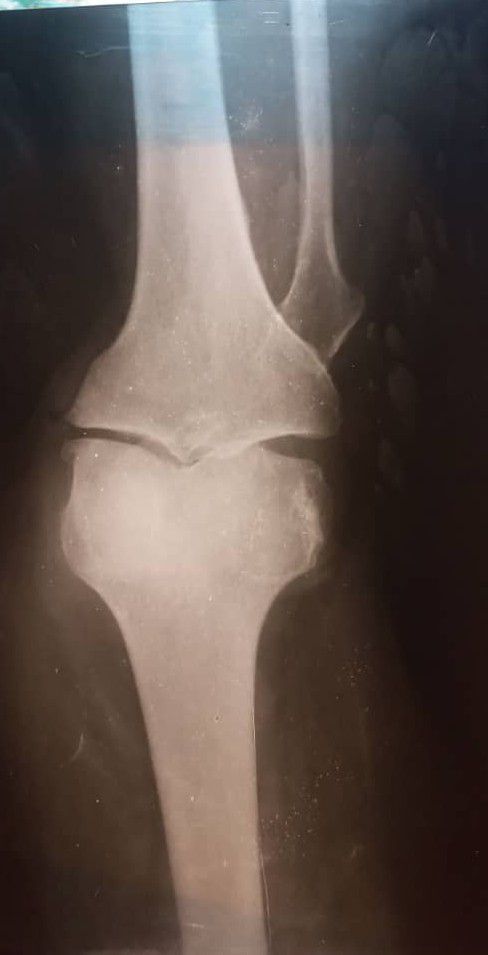

What is your diagnosis?

50 year old woman with knee joint pain, swelling, stiffness?

Osteoarthritis